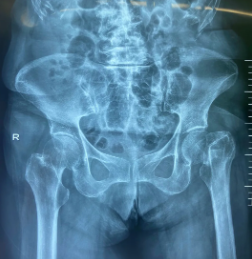

年近八旬的李奶奶几日前不慎摔倒,由于左髋部先着地,因此当时就因疼痛、肿胀导致无法站立,于是急奔以骨科而闻名的betway在线登陆而来。在sararz关节外科,蒋守海主任为李奶奶进行了系统检查,最终确诊为左股骨颈骨折(Garden分型 IV型),需要进行手术治疗。

术前